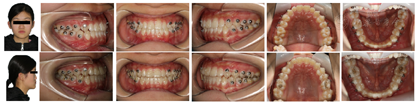

正面观面部不对称,侧面观为凹面型,下颌前突,替牙列,双侧尖磨牙呈近中关系,反覆盖反覆合,Spee曲线深,下颌不能后退至切对切。

治疗前正畸初诊检查包括:模型分析、头颅侧位X光片、全景片、CBCT等诊断为安氏Ⅲ类、以下颌前突为主的骨性Ⅲ类均角患者。

侧貌由凹变直;上下牙排列整齐,牙列无间隙,双侧尖磨牙中性关系,前牙覆合覆盖正常,上下牙弓形态位置关系协调,咬合稳定无干扰。髁突表面发生功能性改建,髁突位置稳定,关节间隙正常。

正面观:面部不对称,左侧面颊部较宽,颏点偏左。侧面观:凹面型,面中份略凹陷,下颌前突,颏唇沟浅。

口腔卫生一般,牙龈轻度肿胀,替牙列期,牙列式:

,其中

反覆合反覆盖。双侧尖磨牙近中关系,反覆盖3.7 mm,反覆合3.6 mm。上中线基本对齐,下中线左偏2 mm。上颌牙弓宽度略不足,下前牙舌倾,根形明显,薄龈型。12,22过小牙。舌体,扁桃体,唇舌系带未见明显异常。

开口度、开口型正常,双侧颞下颌关节无疼痛及弹响。

下颌不能后退至切对切。

总治疗周期30个月,其中TIPA矫治18个月,隐形矫治12个月。矫治后患者侧貌由凹变直;上下牙排列整齐,牙列无间隙,双侧尖磨牙中性关系,前牙覆合覆盖正常,上下牙弓形态位置关系协调,咬合稳定无干扰(图6)。